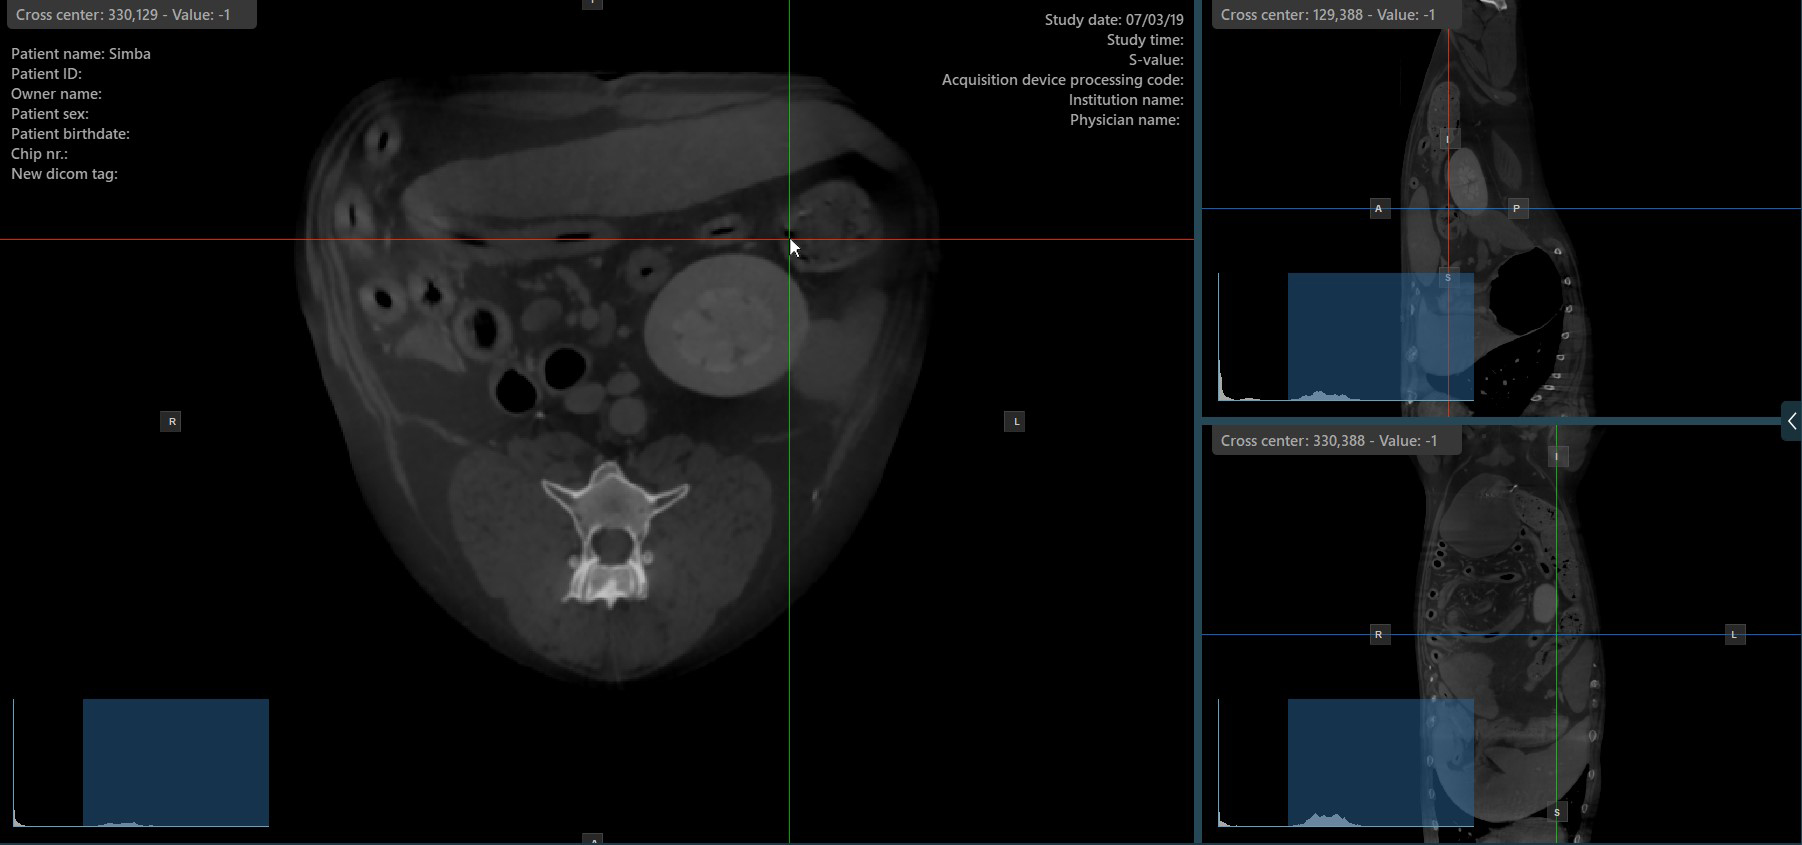

Az MPR nézetben a szeletelők a három kép síkjának metszeteit és orientációját mutatják az aktív nézetablakokban. A felhasználók módosíthatják a szeletelőket, és megváltoztathatják a szeletek keresztmetszeti helyzetét a 3D volumetrikus adatok alapján.

Minden szeletelő a saját, a kép síkját jelző színével van megkülönböztetve:

A kék szeletelő az objektum axiális síkját jelöli (a talajra merőleges).

A piros szeletelő a koronális síkot jelöli (a talajjal párhuzamos).

A zöld szeletelő a szagitális síkot jelöli (a testre merőleges).